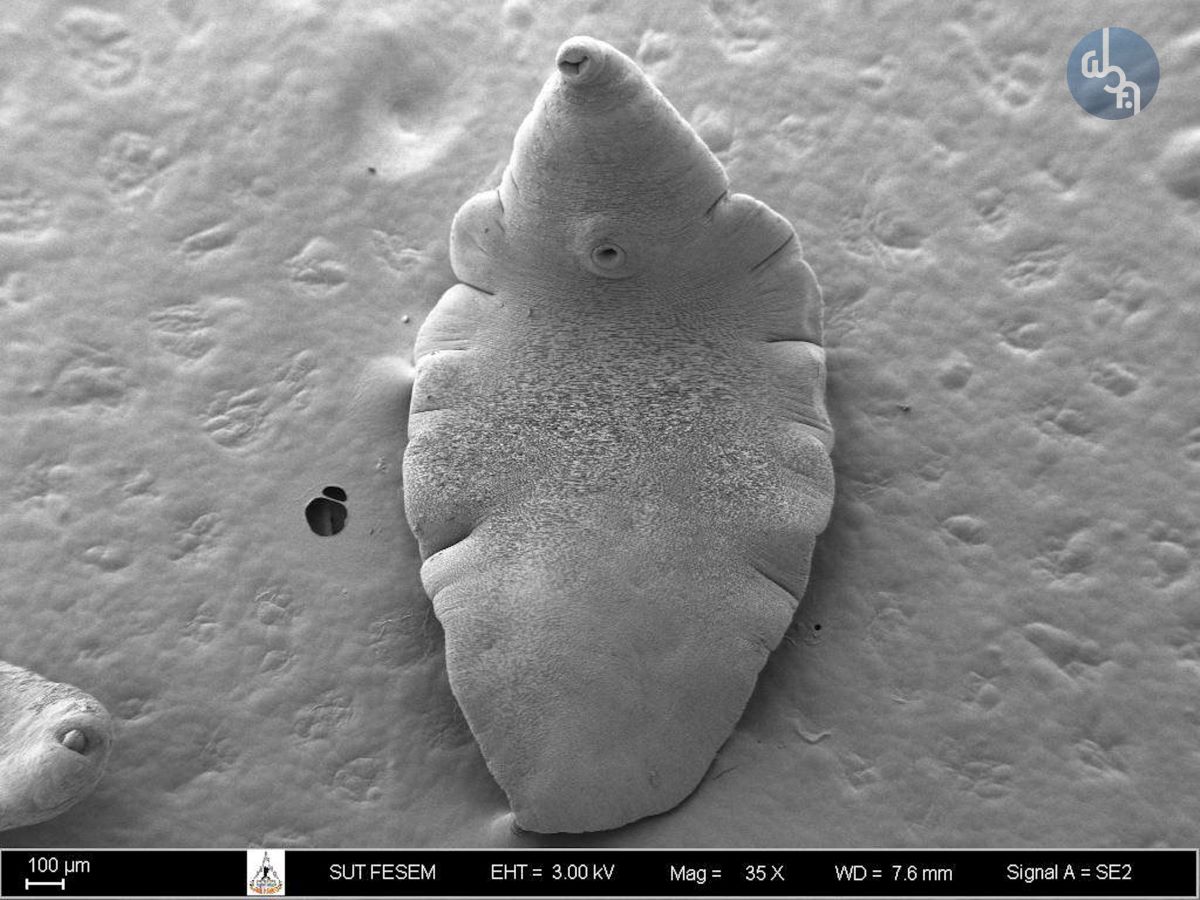

ภาพถ่ายพยาธิใบไม้ในตับ ด้วยกล้องจุลทรรศน์อิเล็กตรอนกำลังขยาย 35 - 1,000 เท่า

“ภาพถ่ายพยาธิใบไม้ในตับ”

ถ่ายภาพด้วยกล้องจุลทรรศน์อิเล็กตรอนแบบส่องกราด

ยี่ห้อ: Carl Zeiss / รุ่น: Auriga

กำลังขยายที่ใช้ถ่ายภาพ: 35 - 1,000 เท่า

อนุเคราะห์ตัวอย่างโดย: สำนักวิชาแพทยศาสตร์ มหาวิทยาลัยเทคโนโลยีสุรนารี

เตรียมตัวอย่างทางชีวภาพด้วยเทคนิค: Fixation  และ Critical Point Drying

เตรียมตัวอย่างโดย: นักวิทยาศาสตร์ประจำฝ่ายวิเคราะห์ด้วยเครื่องมือ (คุณปริญญา พงศานรากุล

ถ่ายภาพโดย: นักวิทยาศาสตร์ประจำฝ่ายวิเคราะห์ด้วยเครื่องมือ (คุณเกวลี พร้อมพิพัฒนพร)